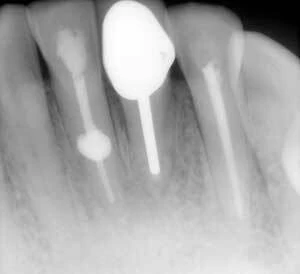

Đôi lúc nứt dọc chân răng hoặc chia chân răng có thể chẩn đoán rõ ràng bằng X quang. Tuy nhiên, hầu hết trường hợp đường nứt nằm trên một mặt phẳng và không nhận ra được trên X quang. Trong một nghiên cứu ở những răng đã được nhổ, các nhà nghiên cứu cho rằng sẽ thấy được vết nứt khi tia X được chiếu trong vòng 4 độ đối với mặt phẳng nứt. Nếu nằm ngoài góc này thì không thấy rõ được đường nứt. Họ cũng nhận thấy rằng nếu có nứt dọc thì chúng chỉ thấy được trên X quang trong 35.7% trường hợp.

Một cách khác để xác định nứt dọc hoặc chia chân răng là quét CAT hoặc dùng phim CBCT. Kỹ thuật này tốt hơn X quang thông thường nhưng ít khi có sẵn trong phòng nha.

Hình 10. Nứt dọc chân răng dẫn đến chia đôi chân răng, điều này có thể phát hiện dược trên X quang

Hình 11. Mặc dù nứt dọc chân răng không phải lúc nào cũng thấy được trên X quang nhưng với một góc chụp đúng thì có thể quan sát rõ đường nứt.